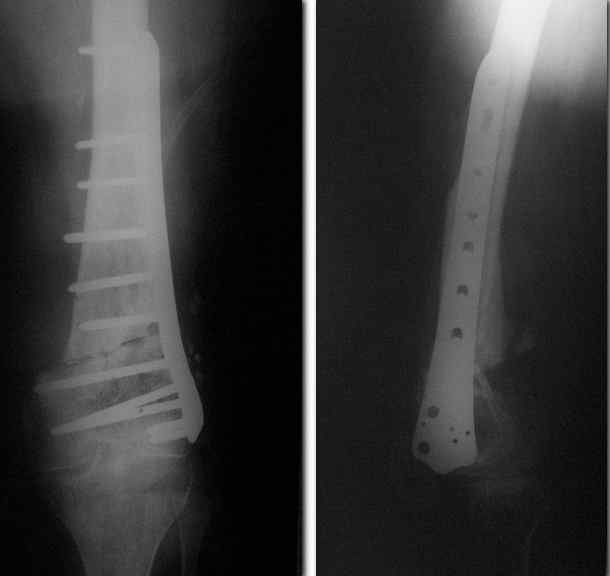

Re: Ложный сустав

Спасибо. Прооперировали во вторник.